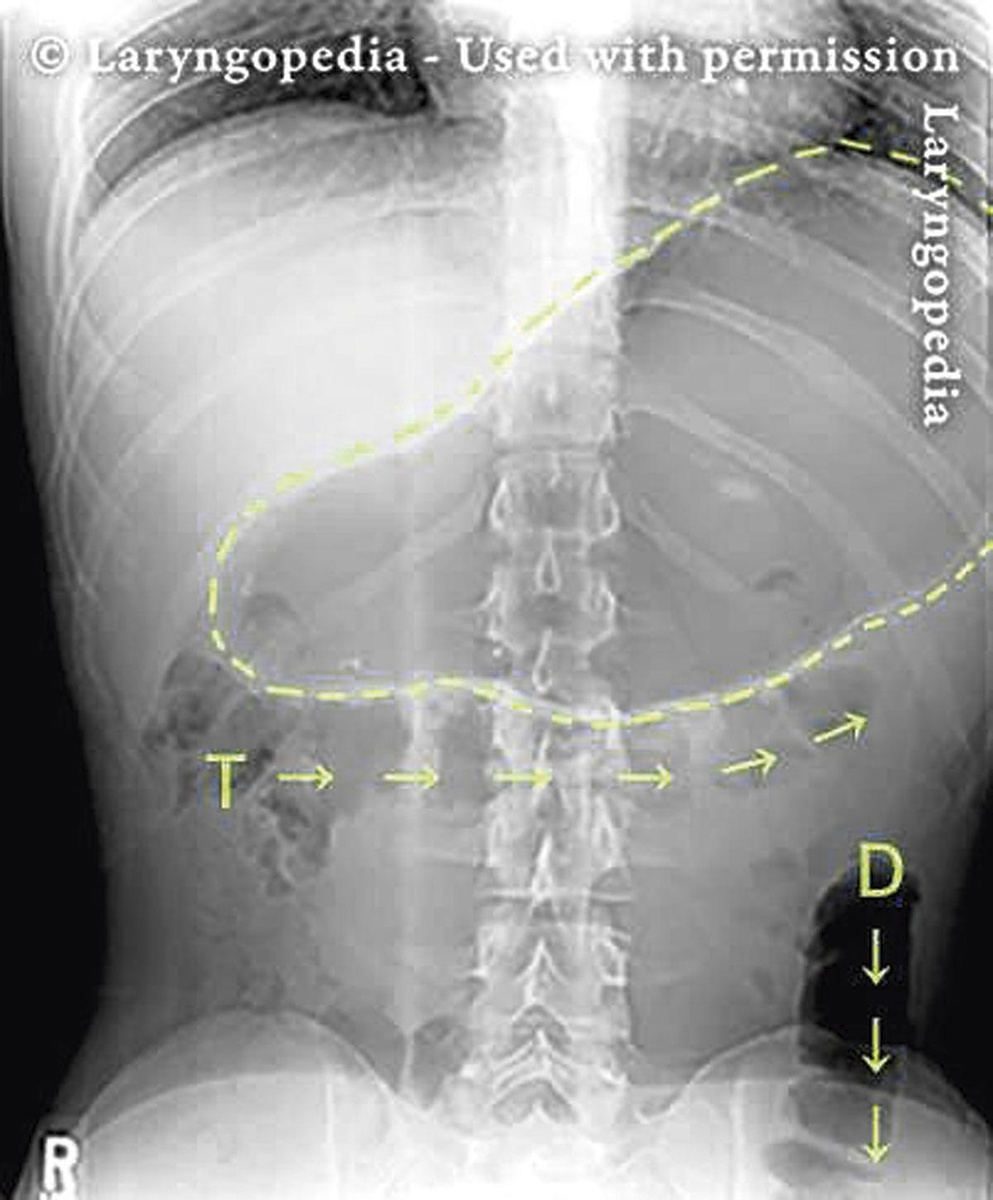

Une fois les aliments dans l'estomac, les sphincters supérieurs et inférieurs de l'oesophage se referment pour éviter les reflux gastriques. Mais ils peuvent se rouvrir pour laisser passer cet air qui doit sortir. Chez les patients qui souffrent de dysfonction rétrograde du cricopharynx, le sphincter oesophagien inférieur s'ouvre correctement, mais ce n'est pas le cas du sphincter oesophagien supérieur, qui reste fermé et emprisonne donc les gaz. Les bulles de gaz s'accumulent alors dans l'oesophage, ce qui provoque des douleurs thoraciques importantes et des bruits typiques, semblables à des coassements de crapauds.

De façon très curieuse, il y a des gens qui ne rotent pas et qui n'ont pas de douleur. Mais ces patients ne représentent qu'une minorité. La plupart ressentent ces douleurs thoraciques, génèrent ces bruits de coassements, et tout se gaz, qui ne peut pas s'échapper par le haut, est éliminé vers le bas. Ils ont des gonflements dans l'abdomen, parce que le gaz traverse tout le tube digestif, et ça provoque alors des douleurs abdominales et des flatulences. Ces patients ont des flatulences toute la journée, ce qui altère fortement leur qualité de vie. Ils n'osent plus sortir au restaurant, ils n'osent plus aller en visite chez les proches, ... J'ai des patients suivis à la clinique de la douleur qui sont sous morphine pour ces douleurs, c'est quelque chose qu'il ne faut vraiment pas sous-estimer.